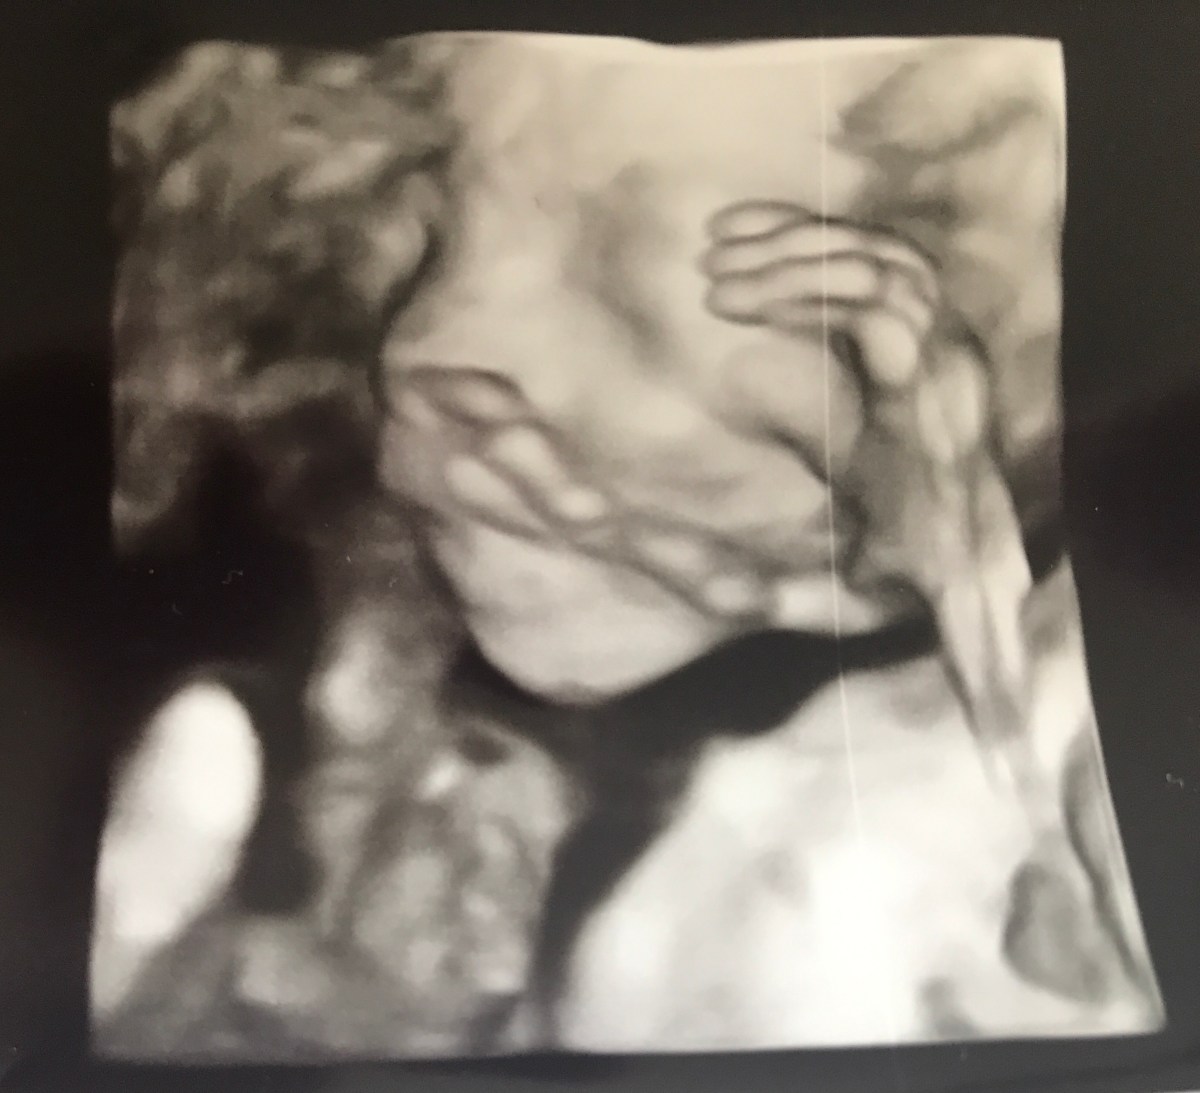

Zoals ik reeds in voorgaande blogs schreef, was het verdict er eentje die me volledig destabiliseerde. Wat al een erg stressvolle periode was vol van angst, maar vooral ook drijfveer van haar, veranderde plots. Al die tijd geloofde ik te moeten vechten omdat zij hier wou zijn, omdat zij perfect groeide en het ongelooflijk goed deed gezien de omstandigheden. Helaas hadden we nog maar eens pech en kwam daar een bijkomend, totaal op zichzelf staand, “issue” bij. En ik probeer het hier bewust wat in een minimalistische context te plaatsen om deze blog niet te zwaarwichtig te maken. Mensen die zich hier helaas in herkennen, zullen dit anders aanvoelen.

De arts begint te kijken op de echo, alles zag er perfect in orde uit. “Jullie weten het geslacht?” Ze grapt nog even in het andere geslacht. De sfeer zit goed. De artsen en wijzelf staan dichter bij elkaar dan ik had kunnen voorspellen. Ik ben geen onbekende, laat staan een nummertje? Neen, ik ben “mevrouw Coppejans met hare percreta”. Ze kijkt rustig verder en geeft aan dat we ook dat “boeleke” eens mogen bekijken en niet altijd die lelijke, tegenwerkende placenta. “Oei, allee wa is da? Das niet goed”. Ik grap nog “wilt uw machine niet mee?” Het antwoord dat ik dan krijg, zorgde ervoor dat het laatste draadje voor Damocles nu echt knapte. Ik voel zijn zwaard, recht door mijn hart. Mijn hart bloedt, onophoudelijk, tot op vandaag.